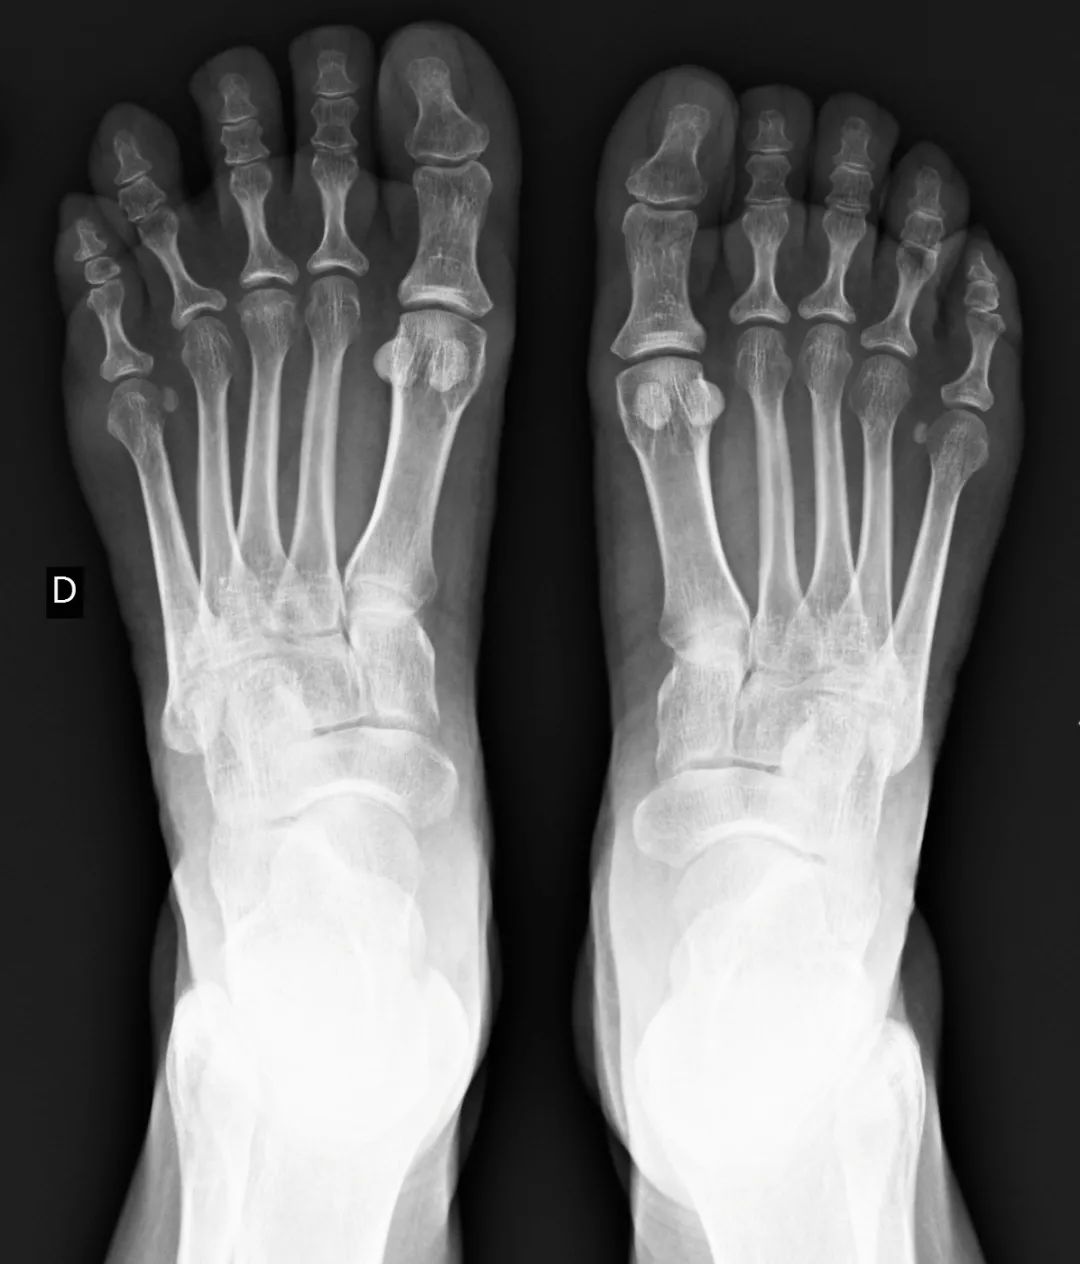

• 扁平足X线测量方法

扁平足X线测量方法

• Freiberg病

Freiberg病